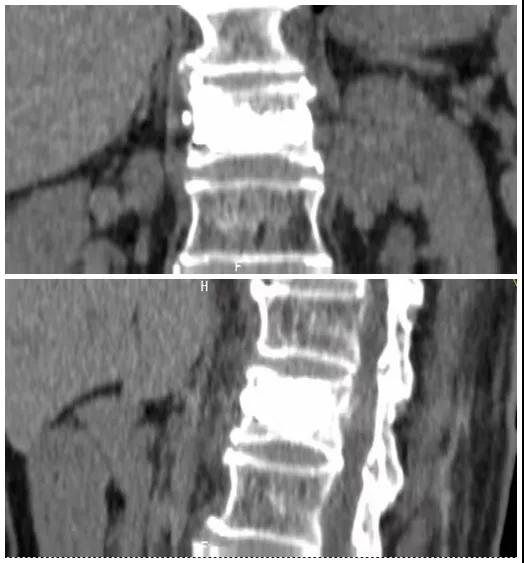

術(shù)前磁共振檢查提示腰1椎體新鮮壓縮性骨折

術(shù)后復(fù)查CT可見骨水泥彌散充分